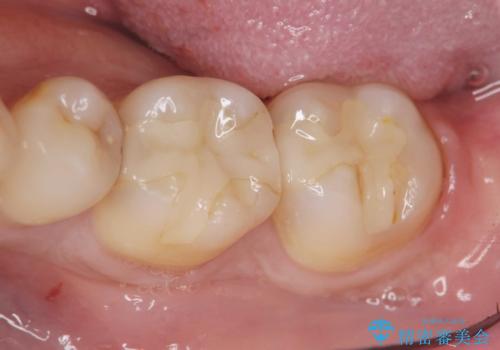

保険適応の白い詰め物レジンインレー下に再発した大きな虫歯治療

- 以前治療した歯の違和感、しみる感じの改善を求めて来院されました。

保険適応の素材、レジン素材による修復が行われていますが、X線写真より修復物の下には透過像(黒い影)が認められ、症状からも虫歯の再発が強く疑われます。